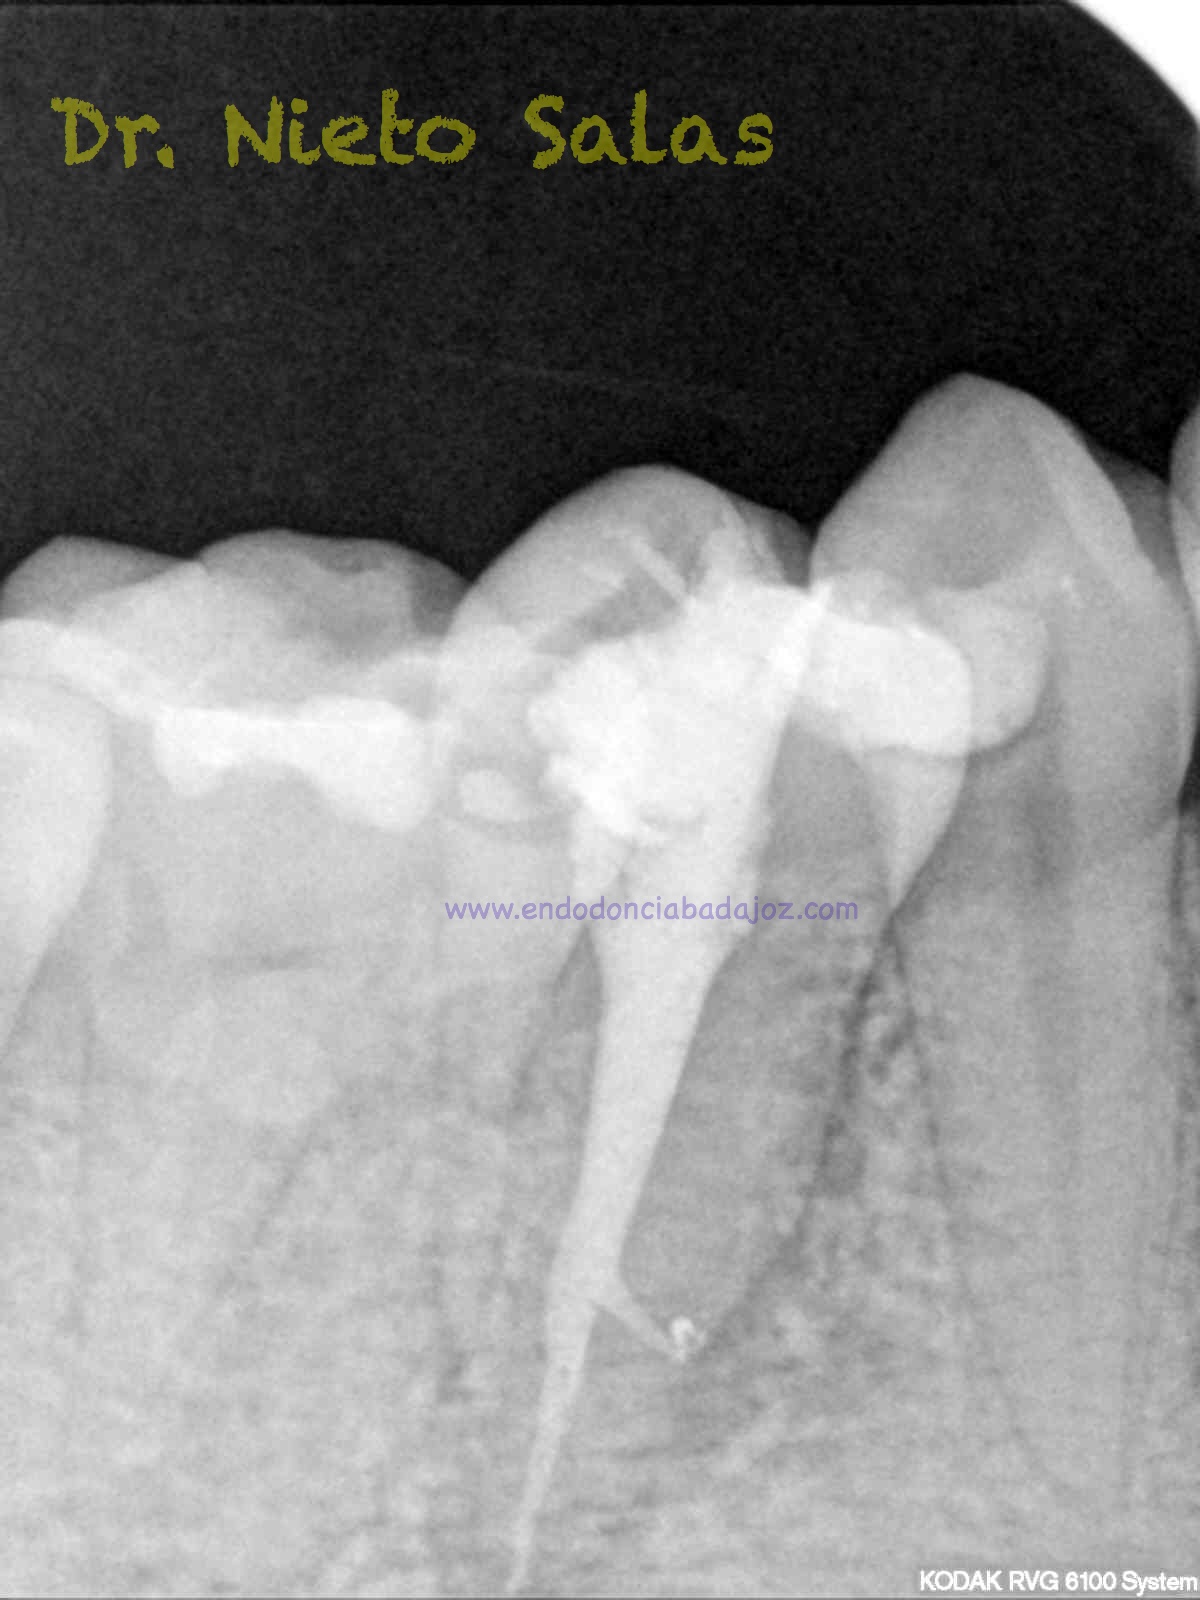

Y este sería el otro caso:

Es muy importante cambiar la proyección de las Rx para tener más información de como hemos sellado el sistema de conductos.

Como sabrás, son muchas las piezas dentarias que presentan conductos laterales, lo primero, es descartar que la imagen pueda ser una fractura vertical, después conformo el sistema de conductos, y si sospecho de un conducto lateral ( INTUICIÓN ) precurvo una lima de pequeño diámetro y exploro las paredes en la zona de puede estar. En ocasiones, puedes ver un pequeño puntito, la entrada, con el microscopio. (es raro).